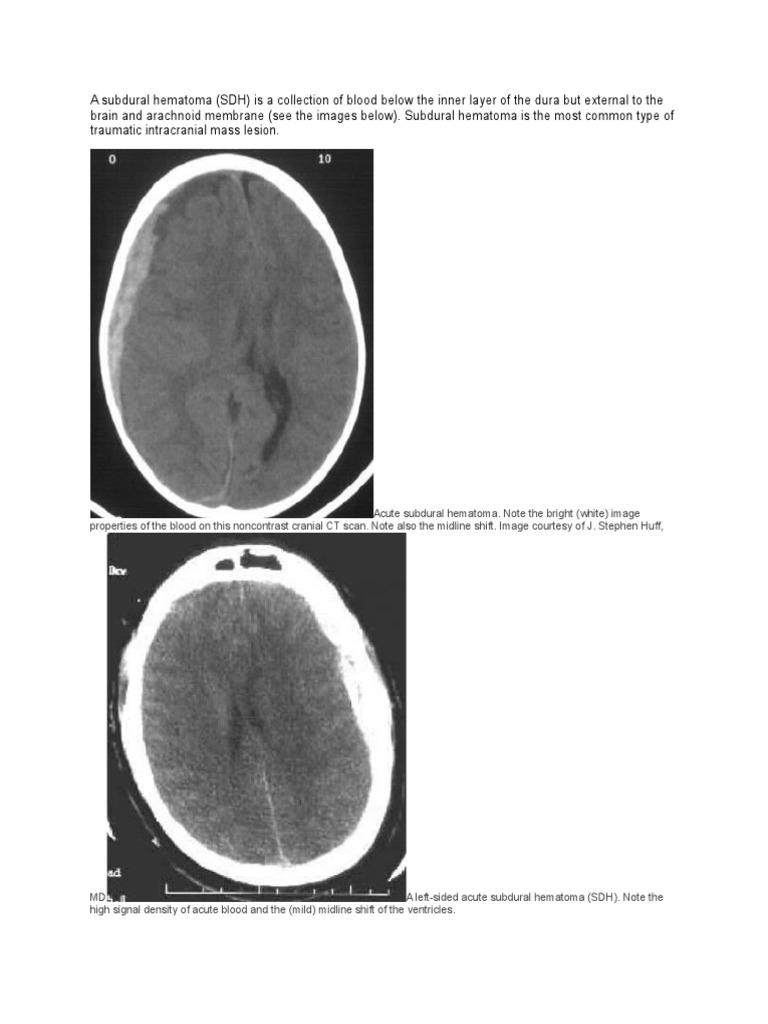

View Brain Trauma Foundation Guidelines Subdural Hematoma Pics. In coma, patients are in a state of deep unconsciousness that lasts for a prolonged or indefinite. Subdural hematoma is the most common type of traumatic intracranial mass lesion.